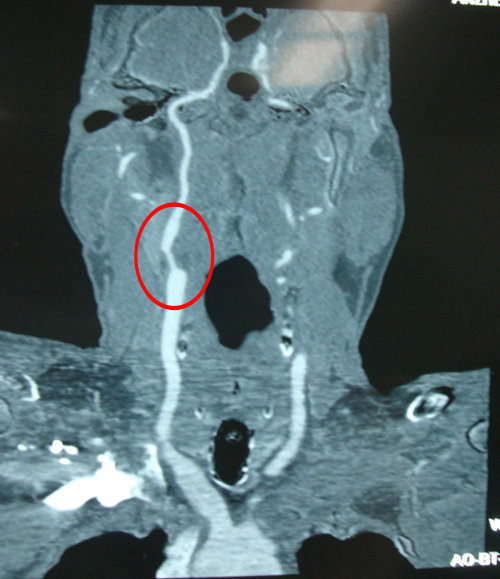

头部血管CT造影:右侧颈内动脉颅内段、右侧大脑中动脉水平段可见节段性狭窄(中度),右侧颞叶、顶叶灌注较对侧偏低。

颈动脉CTA:双侧锁骨下动脉,右侧颈内动脉开口,右侧椎动脉开口局限性狭窄,病原性质考虑动脉硬化性。

双侧颈动脉正位片

右侧ICA